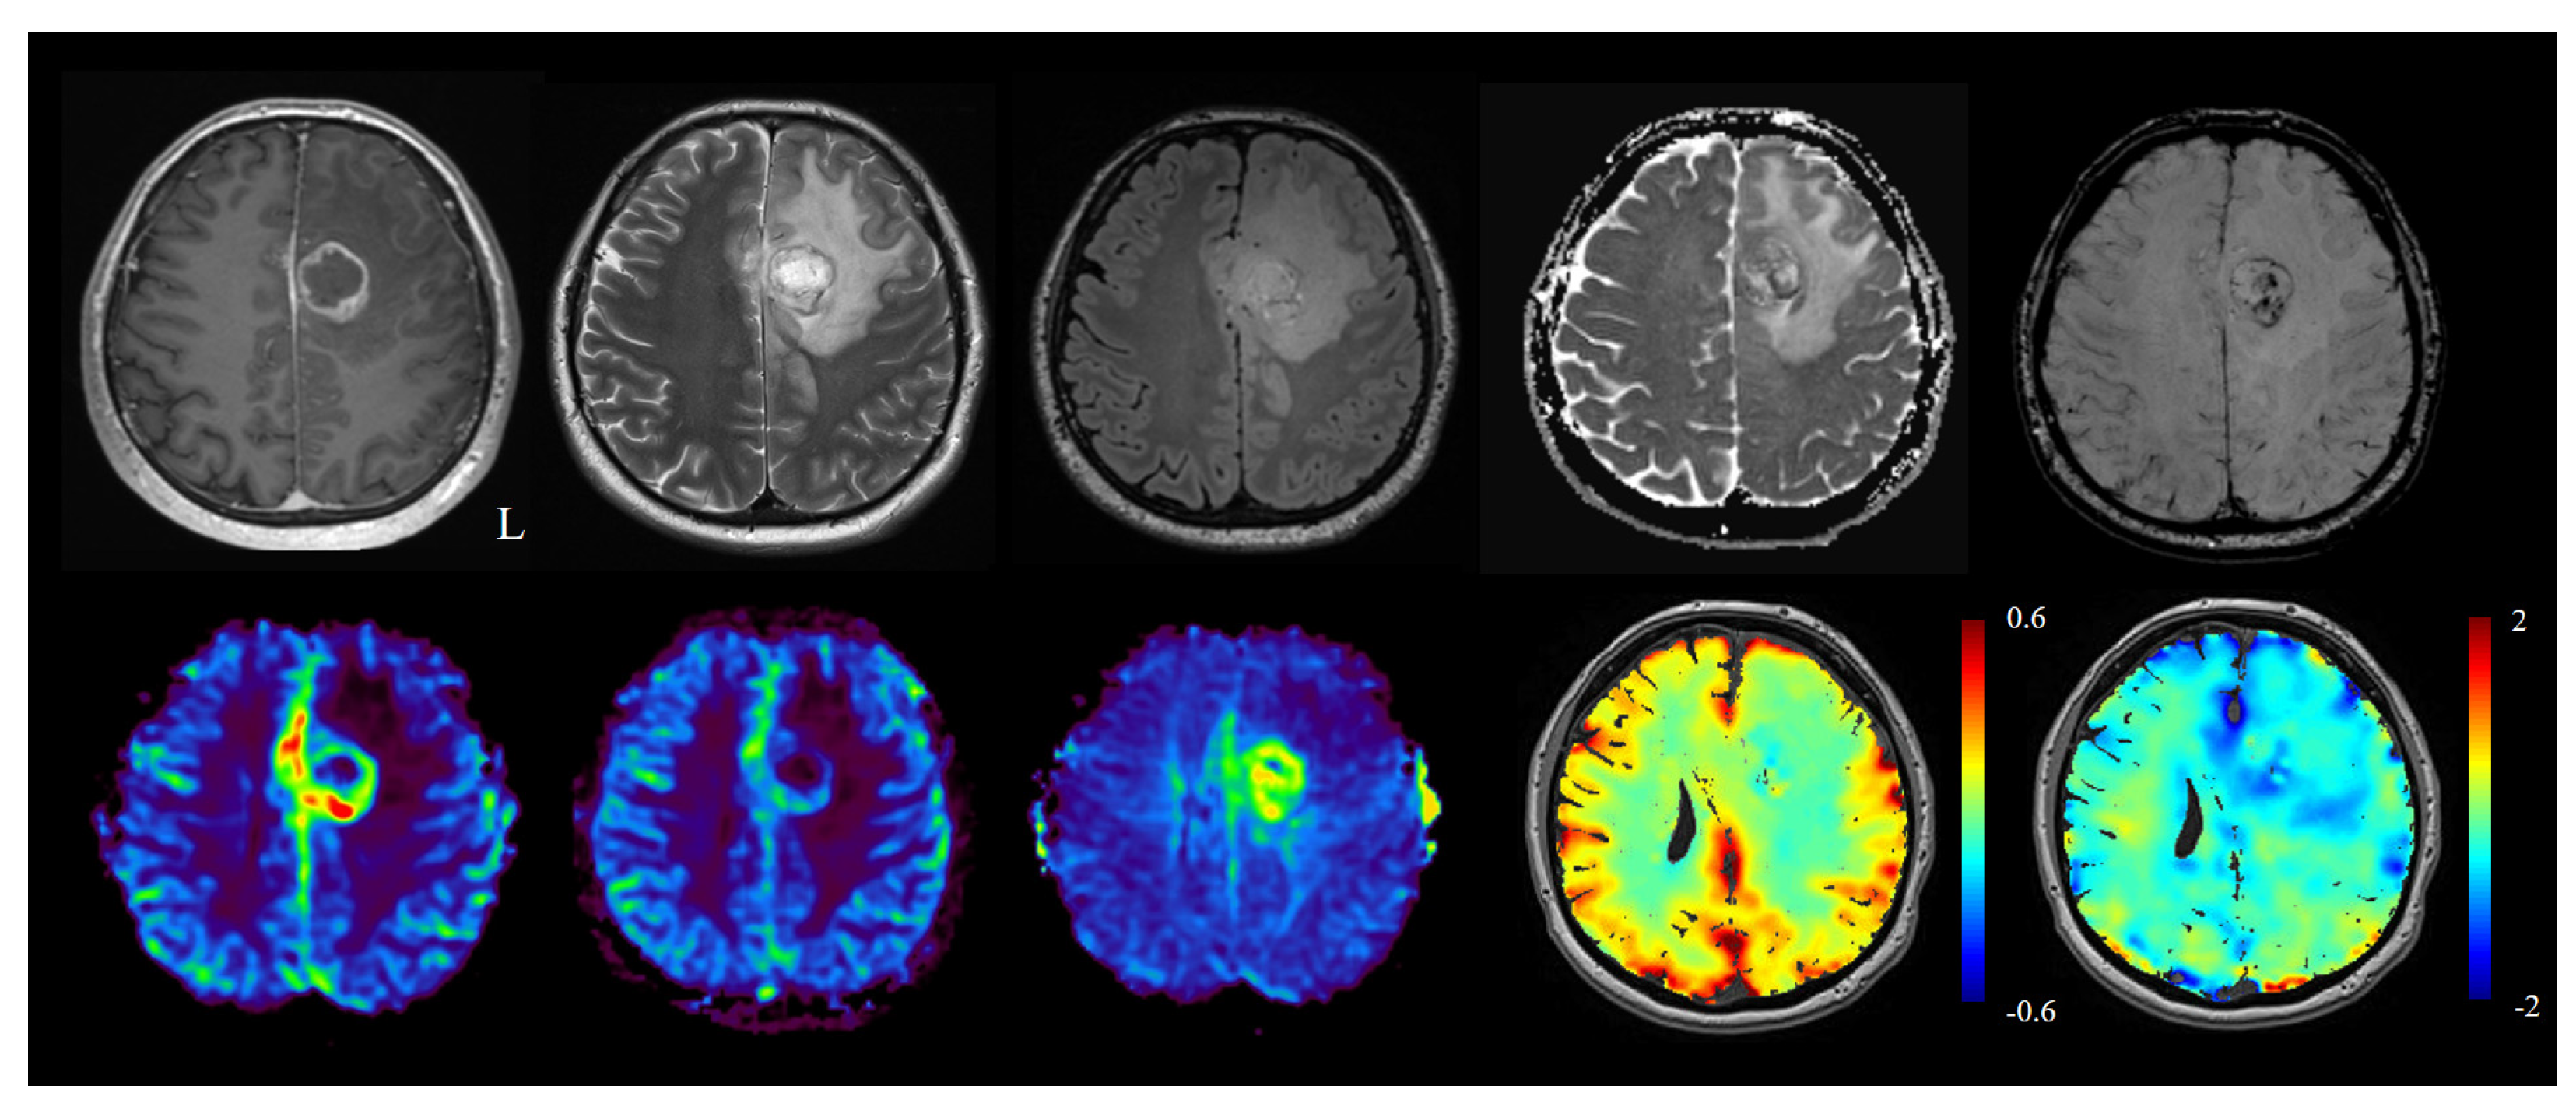

3.4. Gas Modulation and BOLD Imaging: BOLD-CVR and Oxygen Modulation for Enhanced Lesion Characterization

3.5. Machine-Learning and Radiomics

4. Conclusions